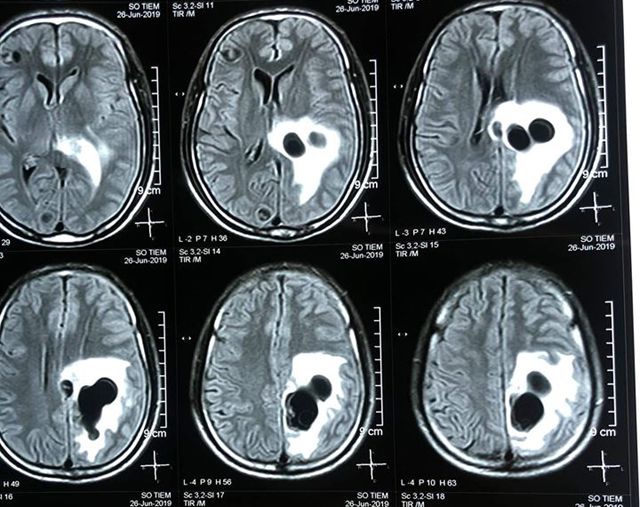

Chỉ là những dấu hiệu bình thường nhưng lại khiến người này bị liệt nửa người. Đau đầu, buồn nôn, sốt, tê liệt nửa người, ông S. được người nhà đưa đến bệnh viện. Kết quả kiểm tra cho thấy bệnh nhân có 5 ổ sán rải rác trong não, gây phù não. Đây chính là nguyên nhân dẫn tới các triệu chứng trên.

Hình ảnh chụp CT cho thấy có nhiều ổ sán nằm rải rác trong não bệnh nhân (ảnh BVĐKNA).

Kết quả chụp CT cho thấy có 5 ổ sán nằm rải rác trong não bệnh nhân, trong đó có một ổ sán lớn trên đỉnh, gây phù não. Bệnh nhân được chỉ định can thiệp ngoại khoa để lấy trọn vẹn ổ nang sán khỏi não. Sau mổ, bệnh nhân hồi phục, tỉnh táo, không liệt, đi lại và sinh hoạt bình thường.